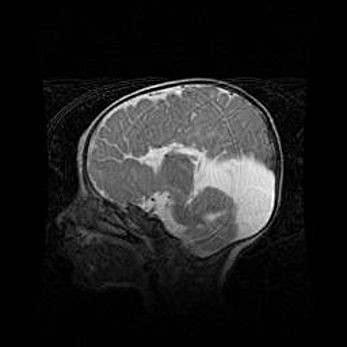

Сообщающаяся гидроцефалия. Кистозная энцефаломаляция головного мозга.

Возраст: 3 месяца 4 дня

Вес: 3100 г

Пол: женский

Окружность головы: 34 см

Срок гестации: 31 неделя

Кистозная энцефаломаляция головного мозга - одна из форм поражения головного мозга в детском возрасте. Характеризуется возникновением множественных и распространённых кист в коре, белом веществе и подкорковых образованиях головного мозга у плодов, новорождённых и детей раннего возраста. Развитие кистозной энцефаломаляции связано с внутриутробной асфиксией и гипотонией, родовой травмой, тромбозом синусов, пороками развития сосудов, инфекциями, сепсисом и другими причинами. Наиболее значимые инфекционные агенты: вирусы простого герпеса, цитомегалии, краснухи, токсоплазмы, энтеробактерии, золотистый стафилококк и другие.